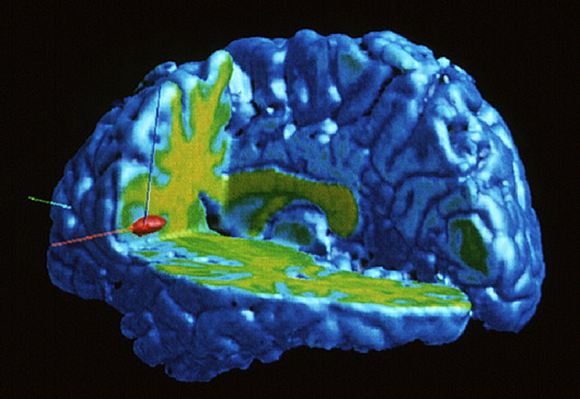

نشرت دراسة في مجلة "سانيس" Science أنّه تمّ العثور على دليل يشير إلى أنّ خلايا النيورونات المرآتيّة تشكّل أساس التّعاطف. وفقًا لدراسة، فإنّ مشاهدة شخص عزيز علينا يعاني من الألم الجسديّ، يؤدّي إلى تنشيط نفس المناطق في الدّماغ، الّتي تنشط عندما نعاني من الألم الجسديّ بأنفسنا. استخدم الباحثون في هذه الدّراسة التّصوير بالرّنين المغناطيسيّ الوظيفيّ (fMRI)، لقياس نشاط الدّماغ لدى النّساء وفيها تمّ تعريضهم لصدمة كهربائيّة مؤلمة في المعصم، وكذلك عندما شاهدن أزواجهنّ يمرّون بتجربة مماثلة. أظهرت النّتائج أنّ استجابة الدّماغ للألم كانت مماثلة في كلتا الحالتين.

يُعتبر الجزءان المسؤولان عن الألم في الدماغ هما القشرة الحزاميّة الأماميّة (Anterior Cingulate Cortex) والقشرة الجزيريّة (Anterior Insula)، وكلاهما يرتبط بالتّمثيلات العاطفيّة والوعي العاطفيّ. تقع القشرة الحزاميّة الأماميّة في الدّماغ بين القشرة الدّماغية والجهاز النّطاقيّ (Limbic System)، المسؤول عن العواطف والدّوافع. بينما تقع القشرة الجزيريّة عميقًا في الدماغ وتعالج الوعي للمشاعر الجسديّة، بما في ذلك الألم. تصل المعلومات الواردة من المناطق النّطاقيّة-العاطفيّة و القشرة الجزيريّة إلى القشرة الحزاميّة الأماميّة، وتساعد جميعها بالاشتراك مع قشرة الدّماغ في اتّخاذ القرارات.

تؤدّي مشاهدة أحد أفراد أسرتك وهو يعاني من الألم الجسديّ إلى تنشيط مناطق الدّماغ الّتي تنشّط أيضًا عندما نعاني من الألم الجسديّ ذاته بأنفسنا. صورة fMRI لدماغ شخص يشعر بالألم (يسار) أو رؤية شخص آخر يعاني من الألم (يمين)| Wellcome Centre Human Neuroimaging / Science Photo Library